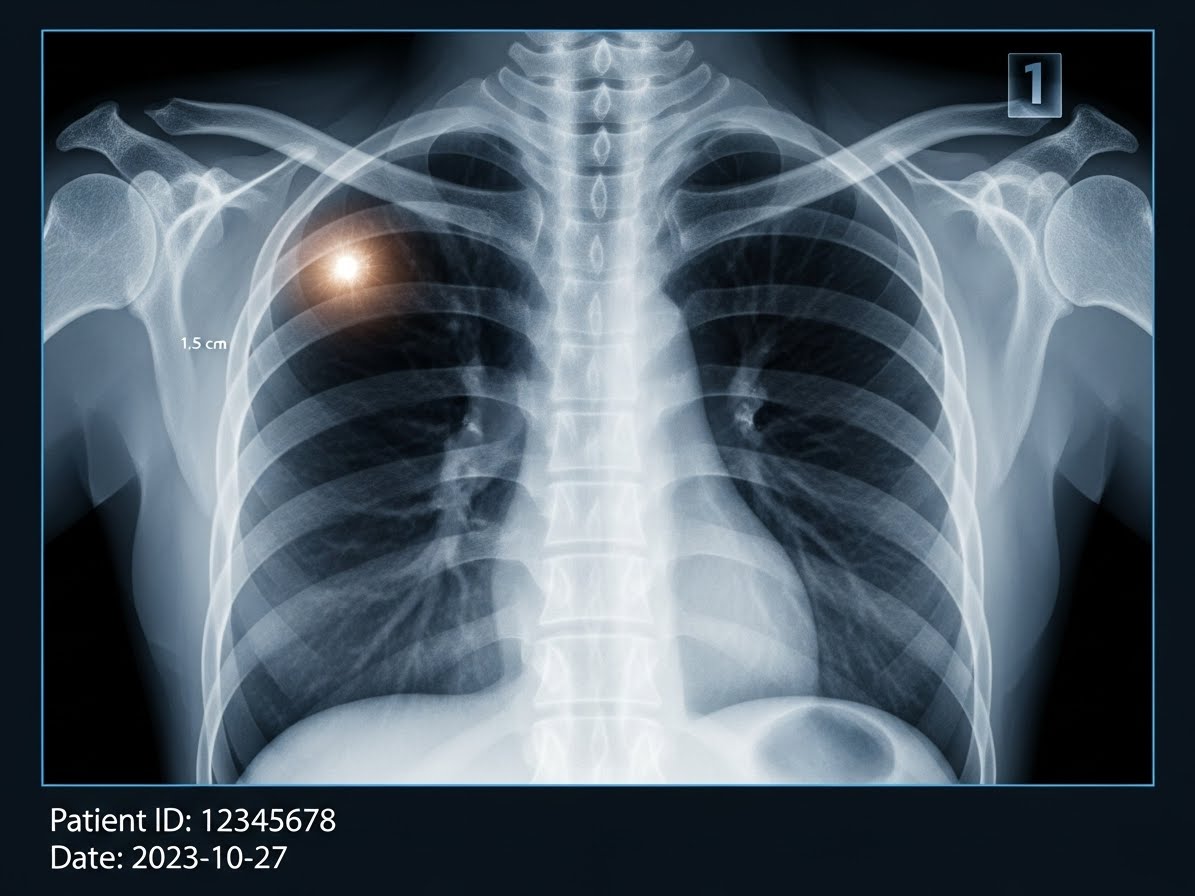

- 흉부 X-ray: 가장 기본적인 검사로, 폐에 이상 소견이 있는지 1차적으로 확인합니다.

- 저선량 흉부 CT: 폐암 조기 진단에 매우 효과적인 검사로, 특히 고위험군(장기 흡연자 등)에게 권장됩니다. 미세한 병변까지 발견할 수 있어요.